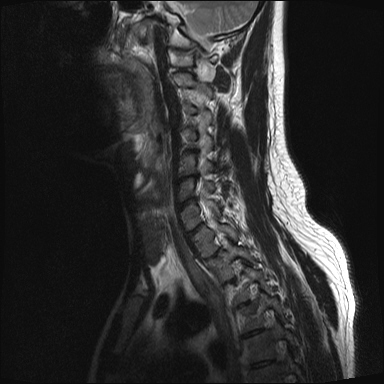

ȸ ϸ鼭 ۼ Դϴ. Ű 172 72 35 ˰Ե ͳ õ ijħ ǥغ ϱ ȣϽ 1C.ڵӸ 1C.ٸǷ 1C.ټ Ǹ 1C.ٱ () 1C.߷ () 1C.Ƿ () 2C.ھȱ, 2C.ڴ 2C.ھ˷⼺(˷) ḷ 2C.ٴ, 2C.ٰḷ 2C., 2C.ٺ, 2C.ٸ 2C.پ˷⼺(˷) 3C.ġ Ű 3C. 4C. 6C.ڸ 6C.ھ Ḳ 6C.ڻ 1T.ȣ 4T. 3T.ȯ, 5T.ȯ ҷ, 6T.ټ 6T.ٽƮ 9T.˷ 10T.ٸǷ 2L. 㰡 2L.ȣ 3L. 3L.ڹ 4L.° 4L.ھƷ 4L.ڿ, 4L.ڵ Ʒ 5L.ڴٸ Ʒκ̳ 5L.ڹ߸̳ õ().¦ٸ ()ũ( ߰Ż) Ը Ͽ ũ(߰Ż), ũ(߰Ż)ġ, , Ḳ , , Ḳ ġ ȱ ǰϰų ڸ, , ڰ , , Ǵ ġ ô ¦ٸ(ٸ̰ ٸ) , 㸮 ̳ ġ Ƹ ġ ħ ߷, , нɷ 帶, ɱٰ, ɺ ڸǥغ ǥغ ϰ ߴ ġ 1. ũ 1) ߺñ: 1 Ӹ ־ ʹ 2)˻ : ** x-ray MRI Ȯ 3,4,5 ũ ̸, Ư 4 ũ ¦ Ƣ . 3)ġ: Ű漺 , ġḦ ʾҰ, Ư ǿ ħ °, Ȱġ(Ȳ,ħ, ȸ ) . 4)ġ : 1.Ͻ ȿ ־, ð 2. 㸮() 1) ߺñ: 3 ϱ ٳѱ⸦ ڱ 㸮 , ģ ƮĪ شٸ 㸮 ȭ ƮĪ Ʋ . 2)˻ : ǿ 㸮 ġ . 3)ġ: ħ ȰġḦ 4)ġ :Ͻ ȿ ־ ɰų 㸮 3. ڰ 1) ߺñ: ڰ̰ ִ Ȯ 5 Ǵܵ 2)˻ : 6~7ð 2~3ð ڸ , ȣ 3)ġ: ġḦ ް , ڰ *** ߿ Ƽ ϰ 4)ġ : ڸ 4. 1) ߺñ: 2~3 ְų Ͻ ־ 2)˻ : ˻縦 ʾ, ʰ ô ó 3)ġ: 4)ġ : 5. ô 1) ߺñ: 3 ڿ ɾƼ ٸ µ ٸ ª 2)˻ : 7 Ȱ X-RAY ణ ô ִٰ Ǹ 3)ġ: ġ 4)ġ : Ͻ 6. (˷ ḷ) ȱ 1) ߺ: 5 2)˻ : Ű 3)ġ:1~2 ѹ ް Ⱦ ֱ ְ 4)ġ : , ħħϰų 7. , Ѽ ȣ ߺñ: ɸ Բ ڰⰡ , ڸ, ä, 2)˻ : Ḧ ʾ, ڰ Ⱑ ư, Ѽ Ҵ Ȳ µ ϰ ȸ ȭ ˷ֽ ǥغ ϴ ڸ ϴ. 㿡 ħ ȸԲ ˷ֽ Ư ġü ġὺƮĪ Բ ġ ȭ ʰ ȸǴ ڼ ϴ ϴ. ˷ֽ ͵ ̳ ǰ ͳݿ ִ ٸ Դϴ. ϴ ȭ Ÿϴ. ϴ. پٰ ϴ. ϴ پų ϴ. 30и 30 ̻ ϶ ϼ̽ϴ. 30иٴ ϰ ҷ ߽ϴ. Ȳ ٷ ϴٰ ٽ ϴ. ķ 鵵 Ÿϴ. γ ȸԲ ڵȽϴ. ٽ ȭּż Ȳ ϰ ʰ ּ̰ ڼ ణ ߸ϰ ־ ֽð ʰ ˷ּ̽ϴ. ȭ Ŀ ߰ ȭ ߾ ߴµ ϴٰ 1 ȭ ѹ ʾҾϴ. ˷ֽ ˷ֽ 뿡 ణ ̴ ε ̼ϰ ٸ ̷ Դϴ. ʰ ϴ ڼ ü ٽ ϰ ˷ּ̰ а ߴص ϰ ˷ֽ θ ϶ ϼ̽ϴ. ˷ֽŵ Ȱ ϰ غ ı øڽϴ. ȸ 㵵 ű Դϴ. ۼ ıԴϴ. http://najari.kr/Board/index.php?Code=free1&No=5141&action=View&st=&sn=&sc=&Keyword=&Page=1 |